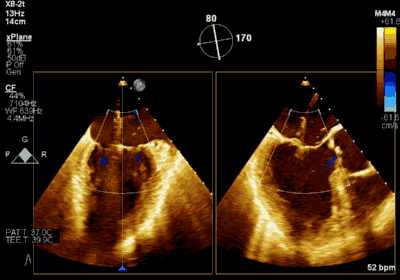

▲ 术前超声检查显示重度二尖瓣反流